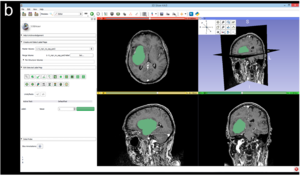

Publication: PLoS One. 2016 Oct 25;11(10):e0164891. PMID: 27780224 | PDF Authors: Fyllingen EH, Stensjøen AL, Berntsen EM, Solheim O, Reinertsen I. Institution: Department of Neurosurgery, St. Olav's University Hospital, Trondheim, Norway. Background/Purpose: To facilitate a more widespread use of volumetric tumor segmentation in clinical studies, there is an urgent need for reliable, user-friendly segmentation software. The aim of this study was therefore to compare three different software packages for semi-automatic brain tumor segmentation of glioblastoma; namely BrainVoyagerTM QX, ITK-Snap and 3D Slicer, and to make data available for future reference. Pre-operative, contrast enhanced T1-weighted 1.5 or 3 Tesla Magnetic Resonance Imaging (MRI) scans were obtained in 20 consecutive patients who underwent surgery for glioblastoma. MRI scans were segmented twice in each software package by two investigators. Intra-rater, inter-rater and between-software agreement was compared by using differences of means with 95% limits of agreement (LoA), Dice's similarity coefficients (DSC) and Hausdorff distance (HD). Time expenditure of segmentations was measured using a stopwatch. Eighteen tumors were included in the analyses. Inter-rater agreement was highest for BrainVoyager with difference of means of 0.19 mL and 95% LoA from -2.42 mL to 2.81 mL. Between-software agreement and 95% LoA were very similar for the different software packages. Intra-rater, inter-rater and between-software DSC were ≥ 0.93 in all analyses. Time expenditure was approximately 41 min per segmentation in BrainVoyager, and 18 min per segmentation in both 3D Slicer and ITK-Snap. Our main findings were that there is a high agreement within and between the software packages in terms of small intra-rater, inter-rater and between-software differences of means and high Dice's similarity coefficients. Time expenditure was highest for BrainVoyager, but all software packages were relatively time-consuming, which may limit usability in an everyday clinical setting. |

Examples of user-interface for segmentation in the 3D Slicer software package. |